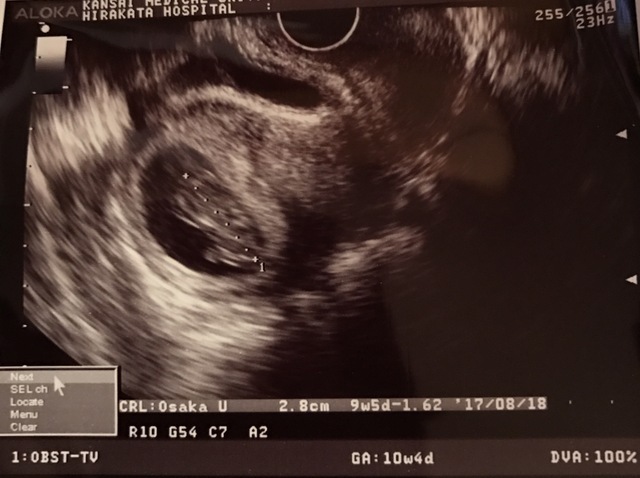

9週1日(9w1d・男の子)|☆ばす☆ さん(27歳)

エコー写真撮影時のエピソード:

お盆に入り暑くて食欲がなくなり、夏バテかな~?と思っていたら、生理のような出血がありました。たんなる夏バテだったんだーと思っていたら、出血が1日で終わりなんか変だなと思っていました。(もともと生理不順のためあまり気にしてませんでした。)

すると本当にどんどん食欲がなくなっていき、すっぱいもの、さっぱりしたものしか受け付けなくなっていきました。気がつけば生理が2ヶ月きていないと思い妊娠検査薬をすると陽性。

つわりだったんだと気が付くと、食欲がなくても大丈夫だったんだ、この子ができたことを教えてくれたんだと思ってうれしくなった、そんな時の写真です!